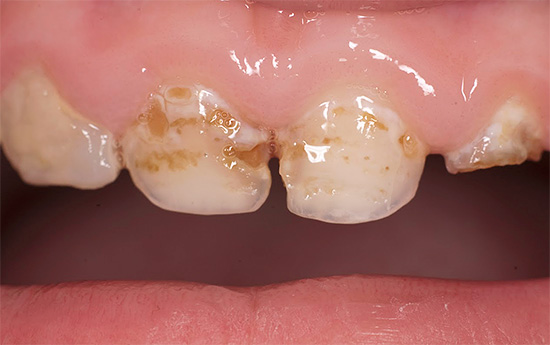

Foto dei denti con carie in bottiglia prima e dopo il trattamento:

Nella foto sotto - tipica carie di bottiglie in una fase avanzata di sviluppo. In alcuni punti, lo smalto dei denti è completamente collassato e sono visibili lesioni profonde della dentina, che si scuriscono rapidamente a causa della pigmentazione di vari coloranti alimentari e prodotti di scarto di batteri:

Nelle prime fasi, la carie di bottiglia può manifestarsi sotto forma di punti chiari opachi (stadio di una macchia bianca o di gesso), che nel tempo assumono la forma di rugosità sullo smalto, gradualmente si approfondiscono e si scuriscono.

Più avanti nella foto - carie media, che copre più denti contemporaneamente. Una tale lesione simultanea è un segno diagnostico caratteristico della carie in bottiglia:

Di norma, la carie di bottiglia colpisce prima i quattro denti superiori anteriori del bambino. Il processo cariato spesso inizia nella zona gengivale, copre rapidamente l'intero dente attorno alla gengiva lungo il perimetro e penetra negli strati profondi di smalto. Il danno alla zona gengivale del dente è una caratteristica della carie in bottiglia.